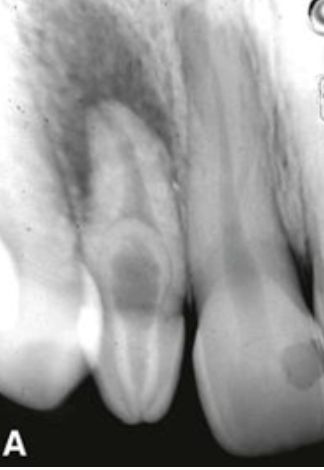

Hierbij is er sneller last van glazuur verlies doordat er een afwijking is aan de dentine. De verbinding tussen het dentine en glazuur is zwakker waardoor het glazuur sneller loslaat. Deze patiënten krijgen niet sneller cariës dan elementen met normale situatie. De mondhygiëne is wel lastiger, door een hobbelig oppervlakte. Dentinegenesis imperfecta is abrasie gevoelig. Vaak hebben ze een afwijkende kleur. Gelukkig heeft het geen verhoogde cariës gevoeligheid. Op een röntgenfoto is vaak een korte radices. Ook zijn er vaak wortelfracturen en zijn het wortelkanaal en de pulpakamer vroeg geoblitereerd.